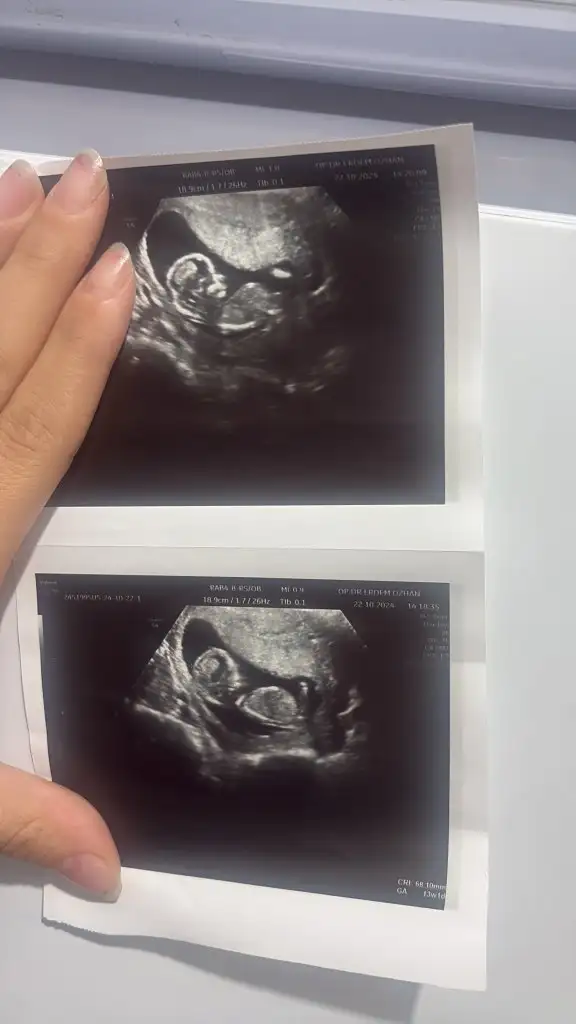

Aramızda çok bu işlerden anlayan varsa

nub Theorisi veya ramzi teorisinden anlayan varsa bana bir tahmin de bulunmak ister mi?

Ultrason 13+2 den. 15 haftalık olunca tekrar gitcem.Eki Görüntüle 3495345

Benimkinide yorumlar mısınızRamzi teorisi için daha küçük haftalardaki yani bebeğin kese içindeki yerleşimine göre bakıyorlar diye biliyorum. 7 ,8 haftalar gibi.

Burda ise eğer gördüğüm nub ise kız bebek tahminim. Gönlünüzce olur umarım

Malesef hiç net değil. Anlaşılmıyor.Benimkinide yorumlar mısınız10+5

Merhaba benim ultrasonu da yorumlar mısınızRamzi teorisi için daha küçük haftalardaki yani bebeğin kese içindeki yerleşimine göre bakıyorlar diye biliyorum. 7 ,8 haftalar gibi.